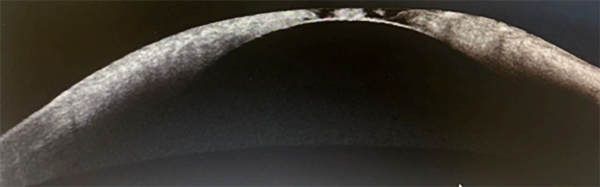

Se completó la exploración realizando una tomografía de coherencia óptica (OCT) de la córnea (fig. 2) que resultó de utilidad para registrar el adelgazamiento paracentral con pérdida de la arquitectura estromal y protrusión del endotelio, compatible con perforación inminente. Se tomaron muestras para descartar patógenos infecciosos y se inició tratamiento médico intensivo con colirios de vancomicina y ceftazidima alternados cada una hora, lubricantes con insulina, atropina al 1% y lubricación frecuente. Se indicó oclusión ocular entre las aplicaciones de gotas y reposo absoluto.

Figura 2. Tomografía de coherencia óptica de córnea donde se observa zona de adelgazamiento y afectación estructural a nivel central.